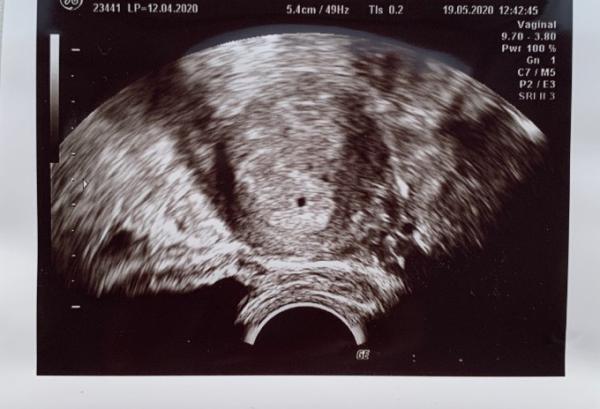

Daraufhin habe ich beim Frauenarzt angerufen und einen Termin für Dienstag bekommen, da ich laut deren Rechnung (erster Tag der letzten Periode) in der 6 SSW wäre. Da auf dem Ultraschallbild für die 6 SSW aber zu wenig zu sehen war, haben wir die SSW erneut aber diesmal nach dem Eisprung berechnet. Demnach wäre ich in der 5 SSW, wonach das Ultraschallbild eher hinkommen würde.

Da hier aber eben fast noch nichts außer ein schwarzer Punkt zu sehen war und man somit auch eine Eileiterschwangerschaft noch nicht zu 100% ausschließen kann, habe ich nächste Woche noch einen Termin, wo ich mich in der 6 Ssw befinden müsste, wo man hoffentlich mehr sieht.

Hat noch jemand bereits so früh einen Ultraschalltermin gehabt und kann sich mit den Bild „identifizieren“?